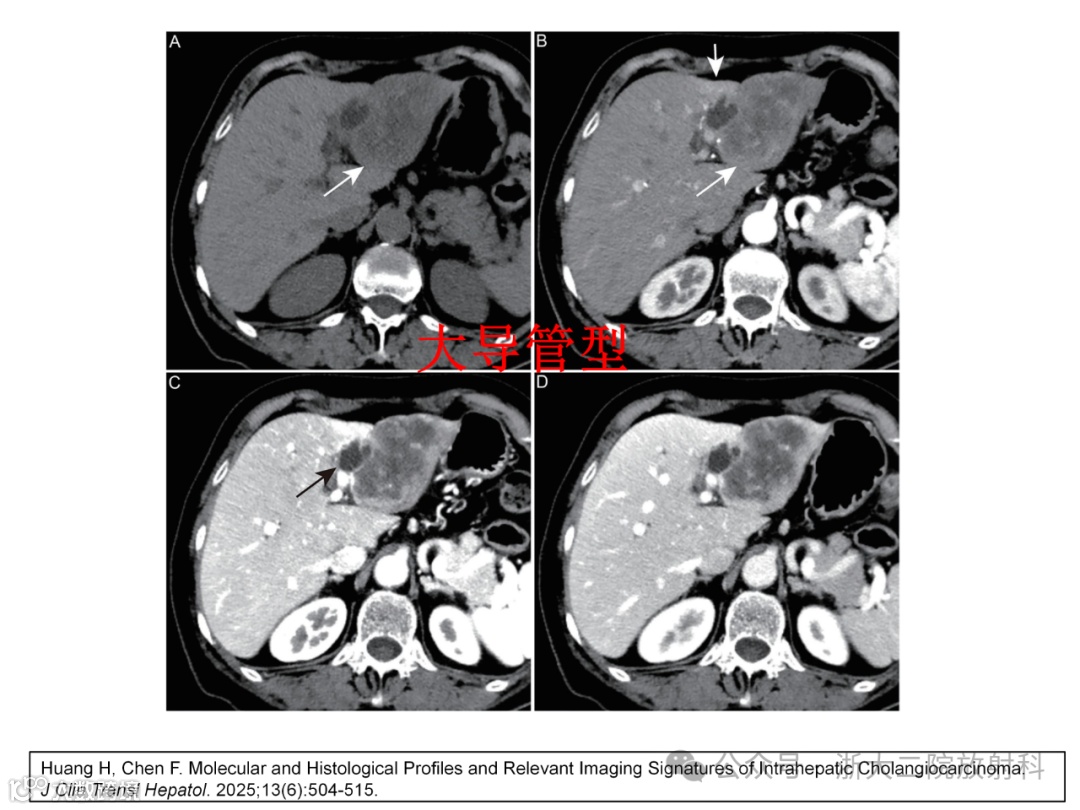

肝内胆管癌的分子特征:在靶向治疗选择中的作用